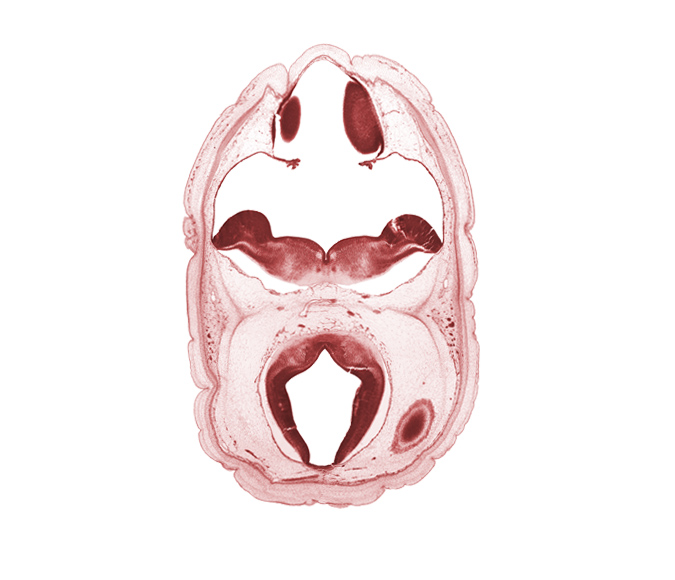

Carnegie Embryo #4090 | Location: 4-19

Keywords: alar plate of myelencephalon, artifact space(s), cerebral aqueduct (mesocoele), cerebral vesicle (hemisphere), choroid plexus, dural band for tentorium cerebelli, median sulcus, posterior cerebral artery, rhombencoel (fourth ventricle), roof plate, roof plate of mesencephalon, sulcus limitans, tectum of mesencephalon, tegmentum of mesencephalon, trochlear nerve (CN IV)

Source: The Virtual Human Embryo.